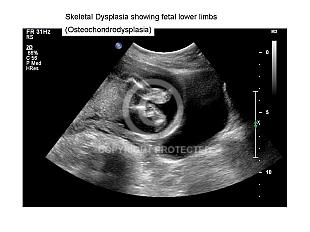

Osteochondodysplasia

Spine and limb anomalies

1019 views